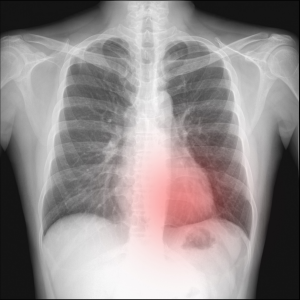

Diseases